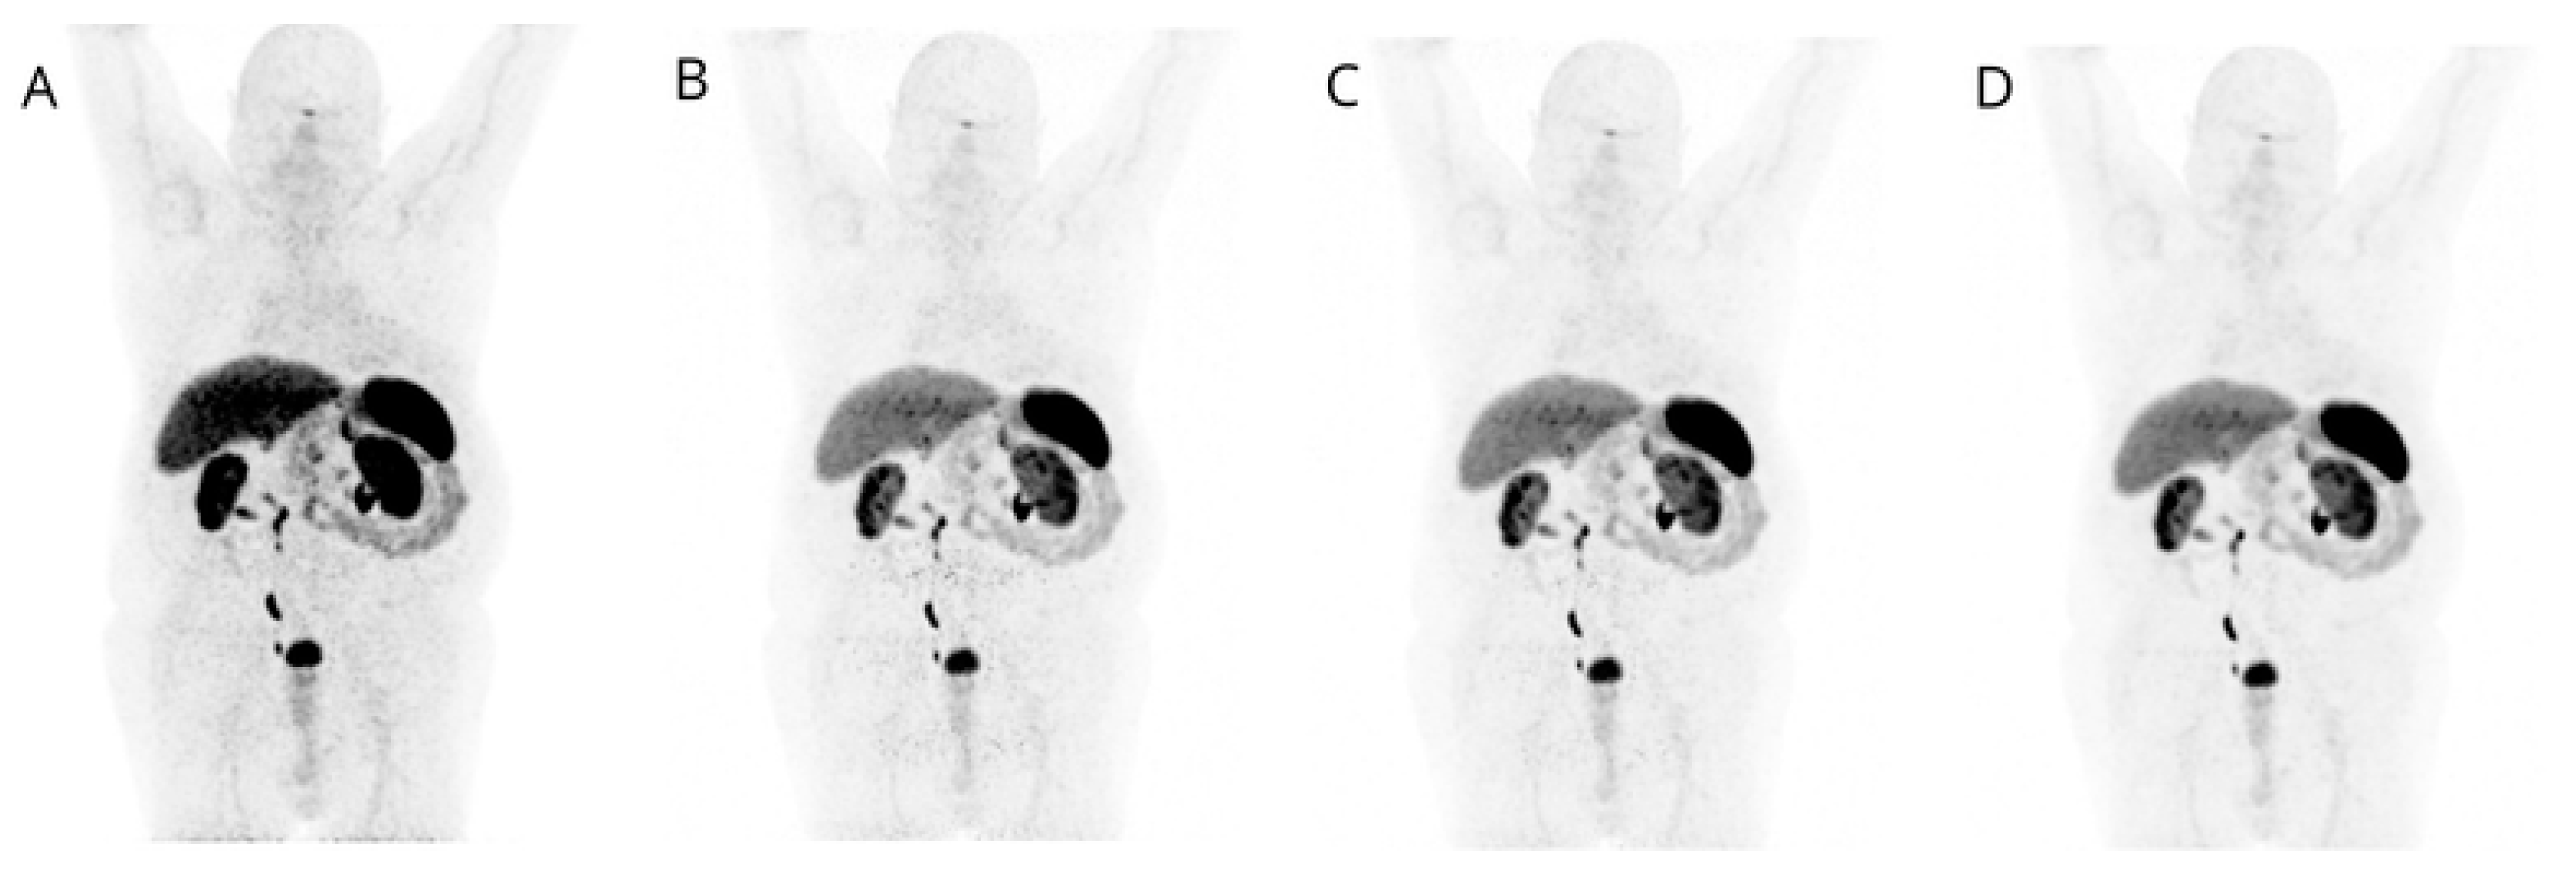

Visual image quality of PET β-1600 reconstruction was considered superior over the others (STD; β-800; β-1000) for both overall scan quality and single-lesion detection in all cases (52/52, 100%), with full agreement between the three readers (100%) (Figure 1 and Figure 2).

Figure 1.

MIP images corresponding to STD (A), β-level 800 (B), β-level 1000 (C), and β-level 1600 (D) are displayed: lower image noise is evident in D, confirming the preferred image quality with β-level 1600.